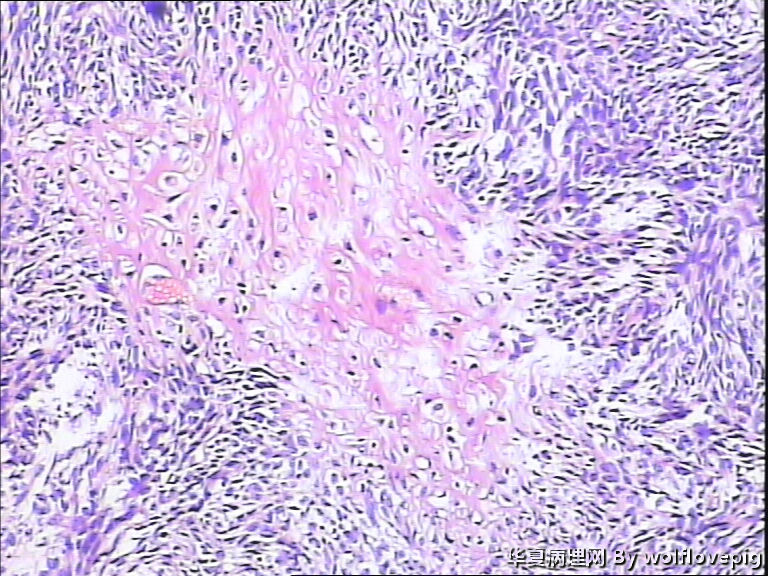

37y,肌壁间可见多个小结节0.2~0.8cm。